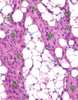

Lipofibromatosis

Fibrous tumor